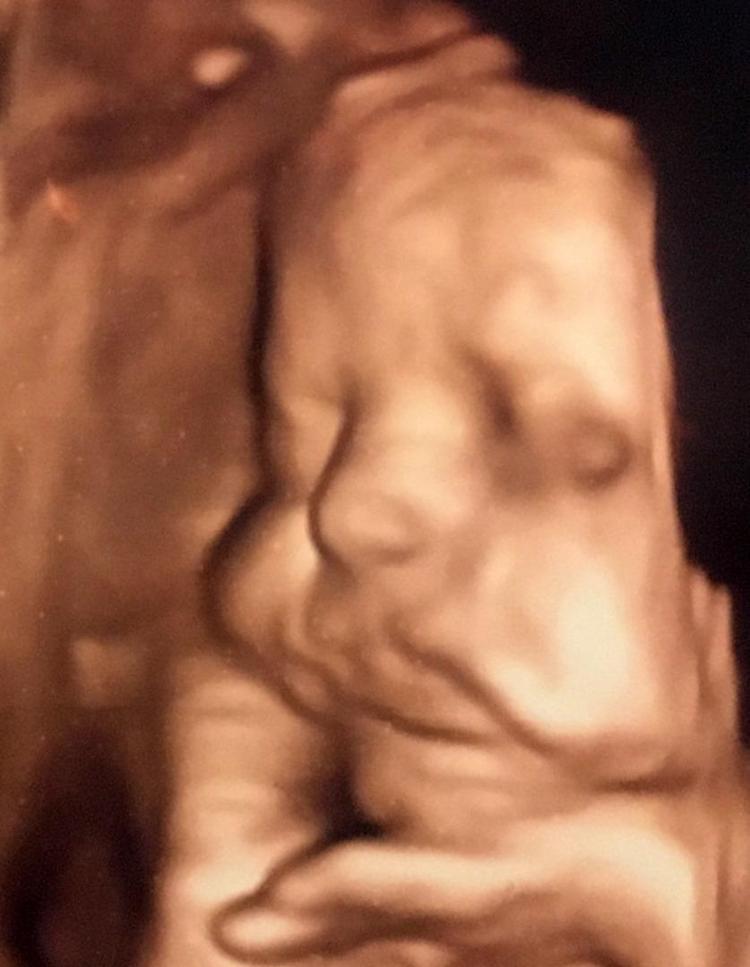

HaberlerFoto Galeri Haberleri Anne karnındaki bebeklerin gülümseten pozları Anne karnındaki bebeklerin gülümseten pozları. • Son Güncelleme: 20 Şubat 2020 - 09:11 • Son Güncelleme: 20 Şubat 2020 - 09:111 23456789101112